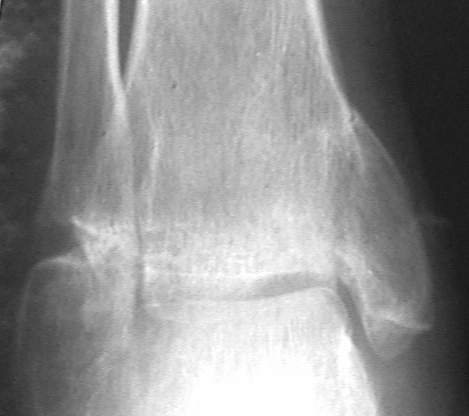

Ложный сустав лодыжки

У больного травма в августе 2001 г. Лечился консервативно, Проводилась иммобилизация гипсовой лонгетой 3 мес. В последующем местное лечение. Остается контрактура боли в области наружной лодыжки. Направлен в наше отделение в конце января 2002 г Планируется костная аутопластика, остеосинтез пластиной, винтами перелома наружной лодыжки. Решается вопрос о коррекции неправильно сросшегося перелома внутренней лодыжки. Рентгенограммы: фас; профиль; план Сергей Зырянов